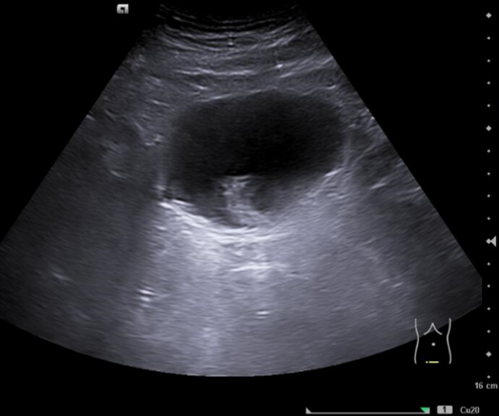

En ecografía clínica de aparato urinario se objetiva a nivel de vejiga imagen hiperecogénica dependiente de pared que no se moviliza con la movilización del paciente y no capta con modo Doppler color.

Ecografía aparato urinario agosto 2024: Litiasis en cáliz medio izquierdo de 6 mm, lesiones vesicales, próstata de 45 g.

Cistoscopia agosto 2024: Descripción de hallazgos vesicales: Lesión papilo-sólida en fondo vesical con calcificaciones en su superficie, de aproximadamente 1-1,5 cm de tamaño.